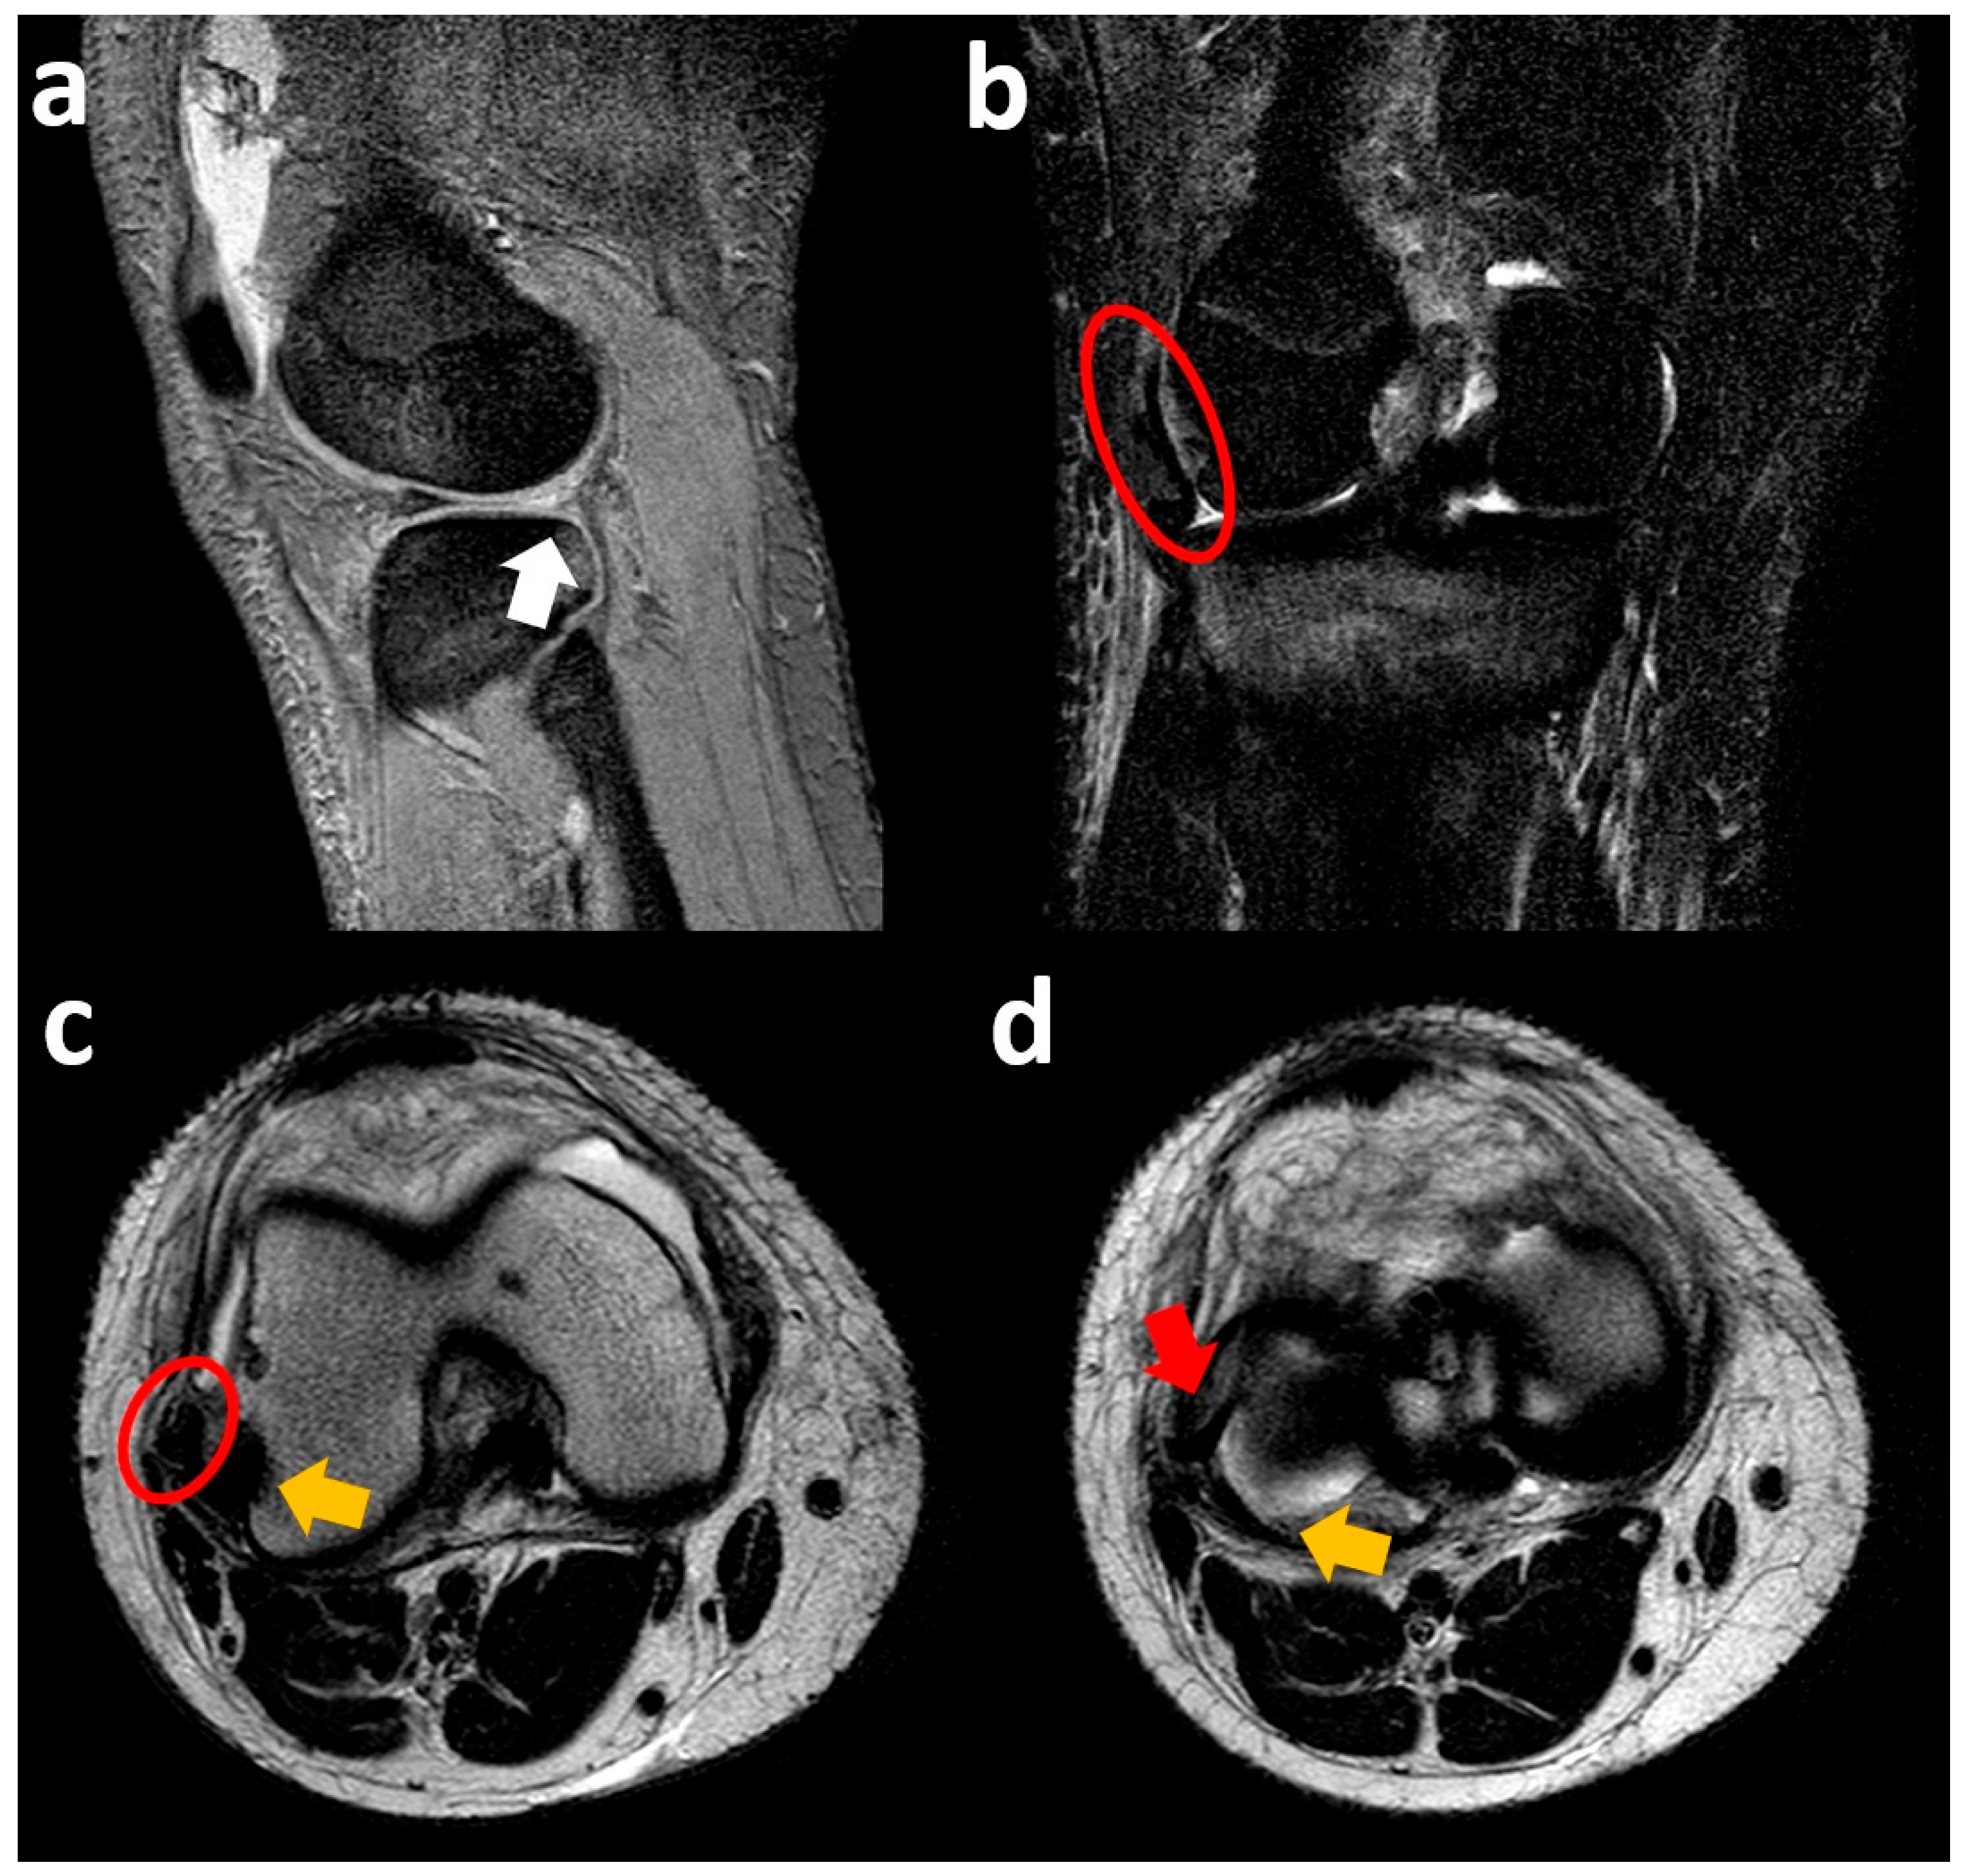

3.2. Medial Meniscus Radial Tear with Flipped Body

3.3. Medial Meniscus Posterior Root Tear with Extrusion